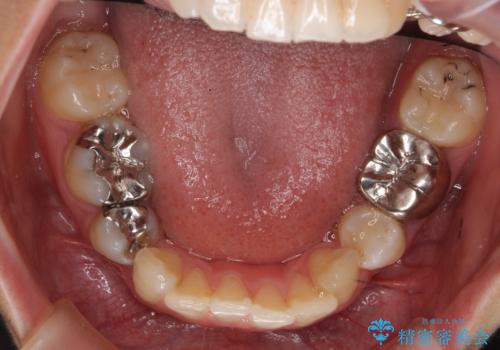

- 左下の銀歯の状態が悪く抜歯してブリッジにした患者様です。

全体矯正治療の経過は以下です

https://seimitsushinbi.jp/case/104145/